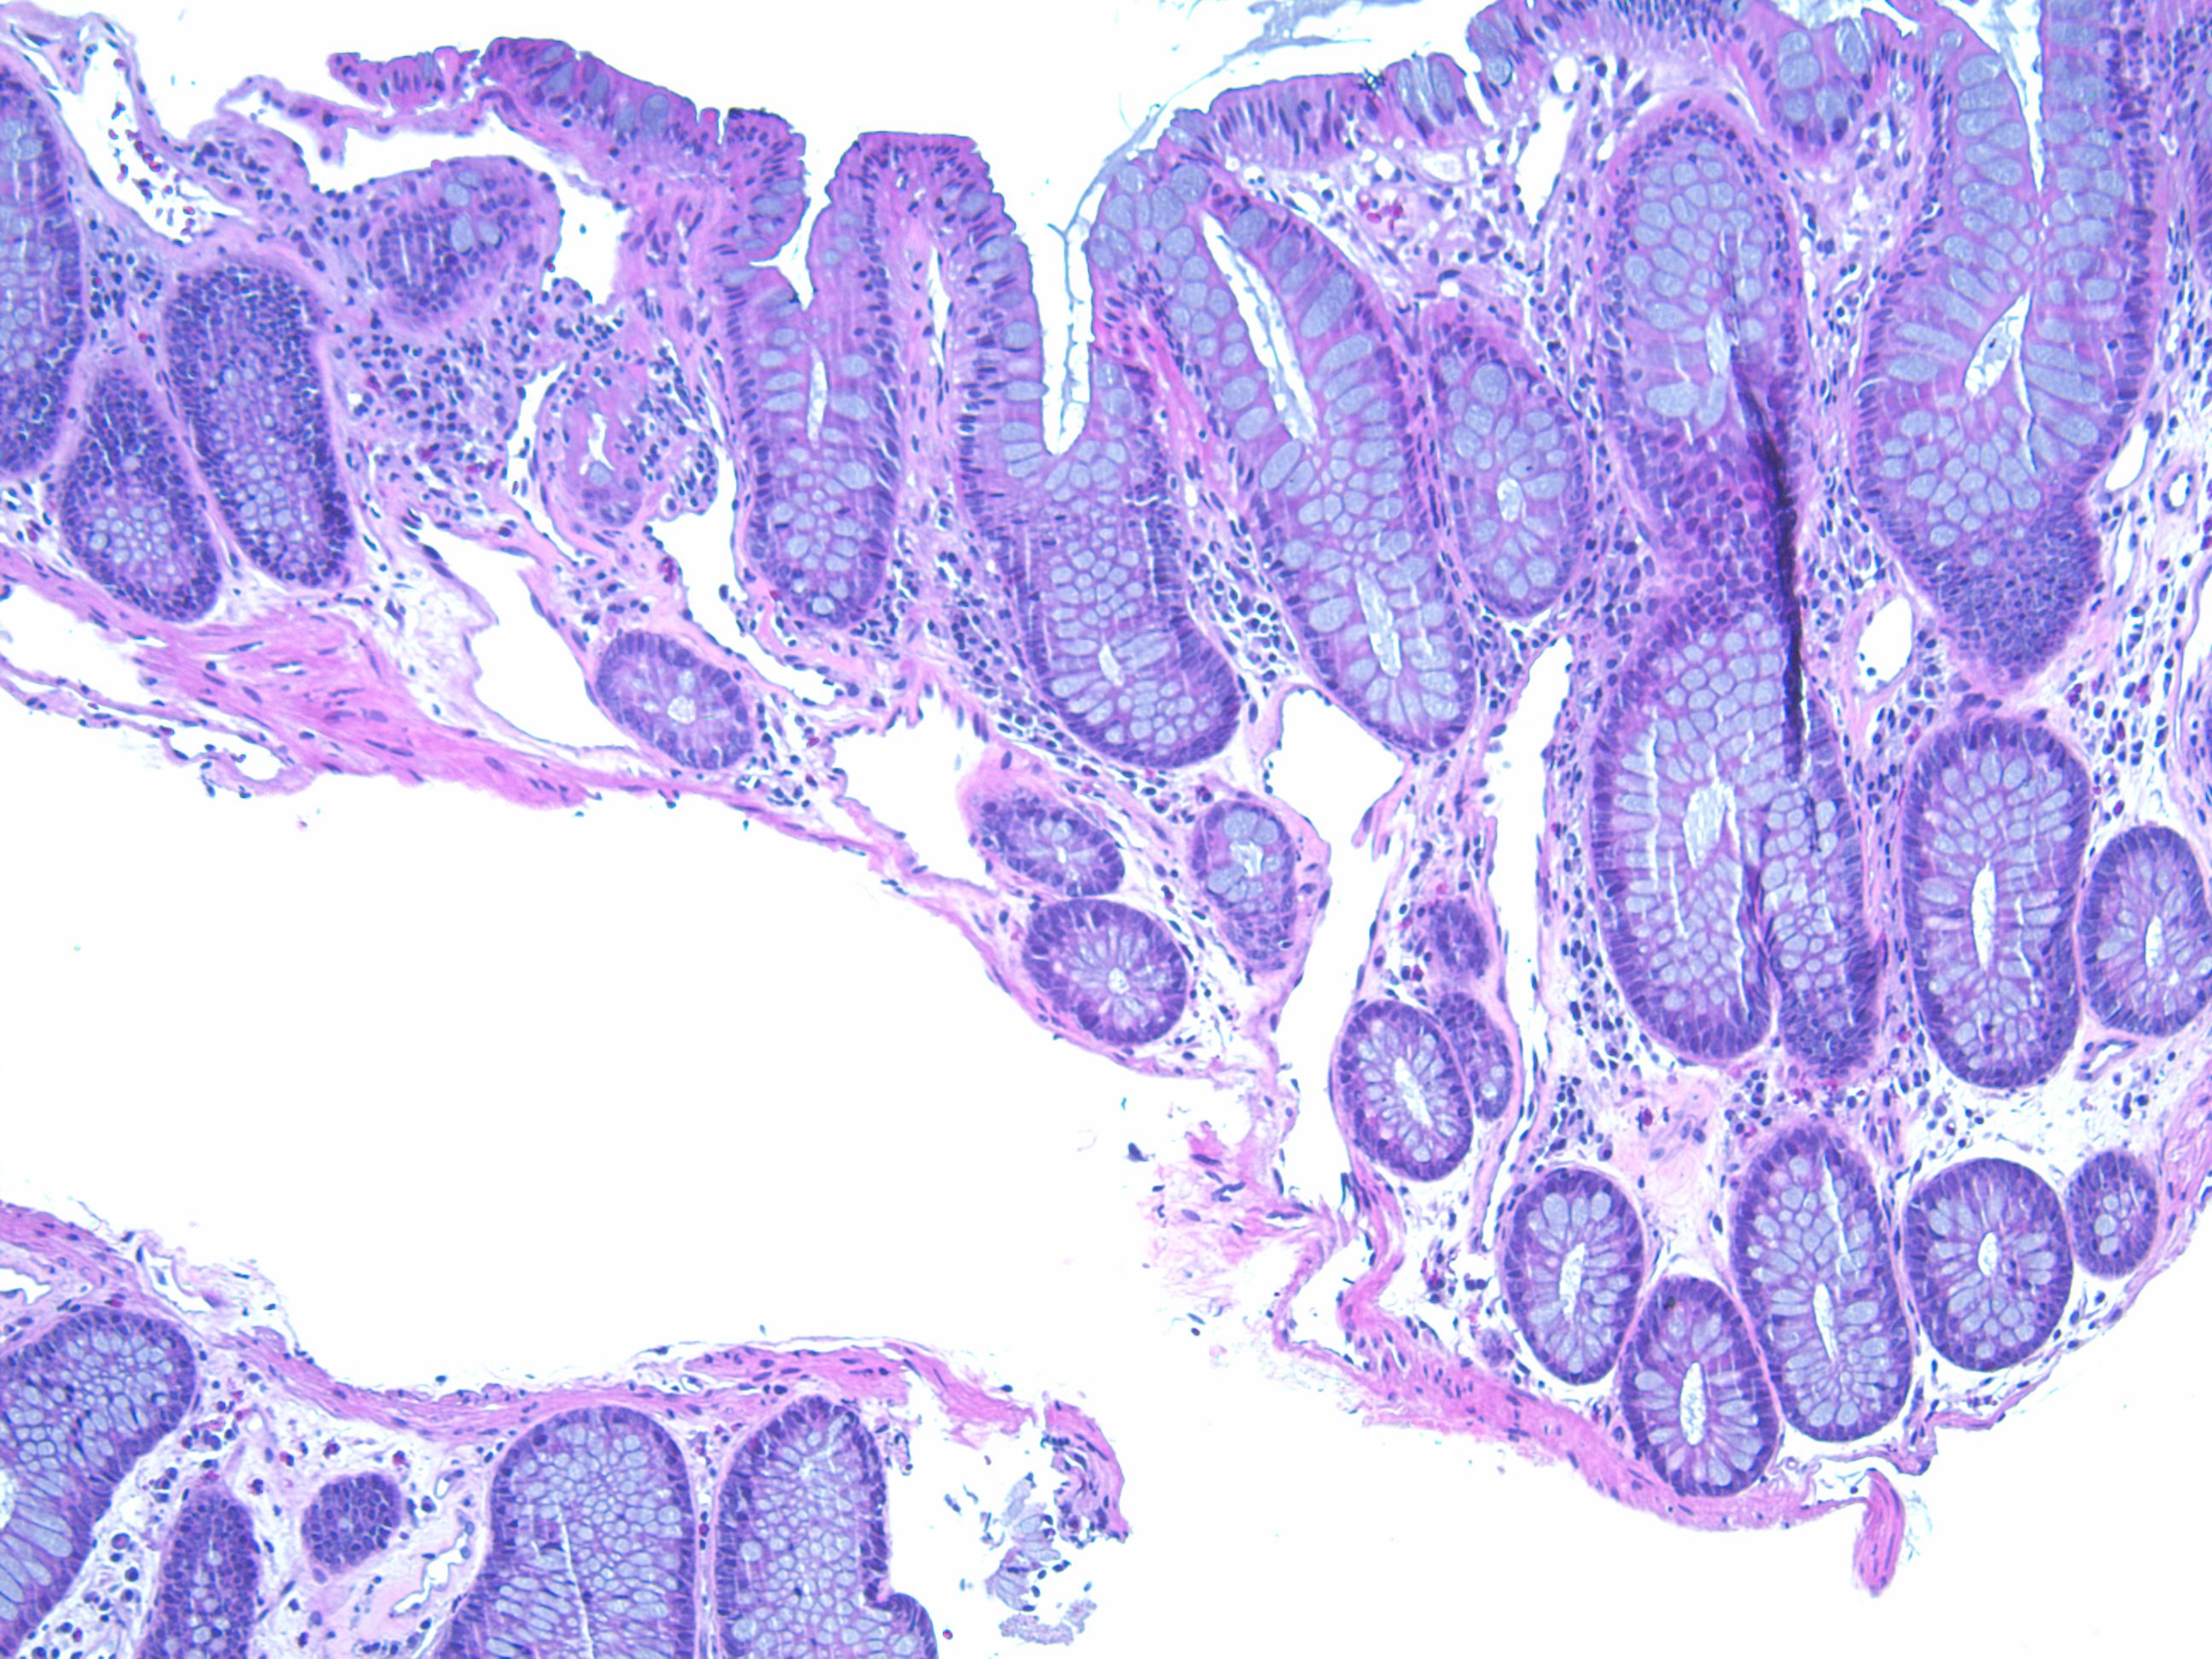

组织学上急性损伤黏膜及固有层嗜酸性粒细胞浸润,隐窝受损及萎缩类似于霉酚酸酯结肠炎或移植物抗宿主疾病,少数活检时处于自限性状态。慢性改变可见毛细血管扩张伴不典型性内皮细胞,固有层及血管玻璃样变,不典型间质细胞(放射性的纤维母细胞),损伤愈合后可见腺体结构变形类似炎症性肠病,肠壁深层动脉受损可见内膜增生、血栓形成及纤维化,动脉受损导致缺血的改变,瘢痕的形成。纤维化及瘢痕的形成引起小肠梗阻及继发性细菌繁殖。

部分病例放射之后可见深部囊性结肠炎及少数报道小肠内泡沫巨噬细胞聚集。